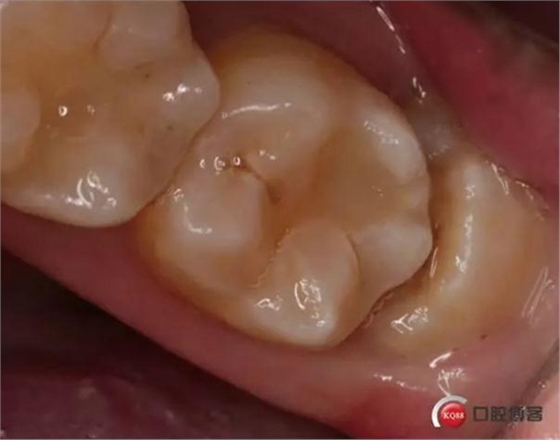

檢查:口內(nèi)可見38未完全萌出,無松動,周圍牙齦顏色正常,叩診(—)觸診(—),X線顯示近中阻生,雙根